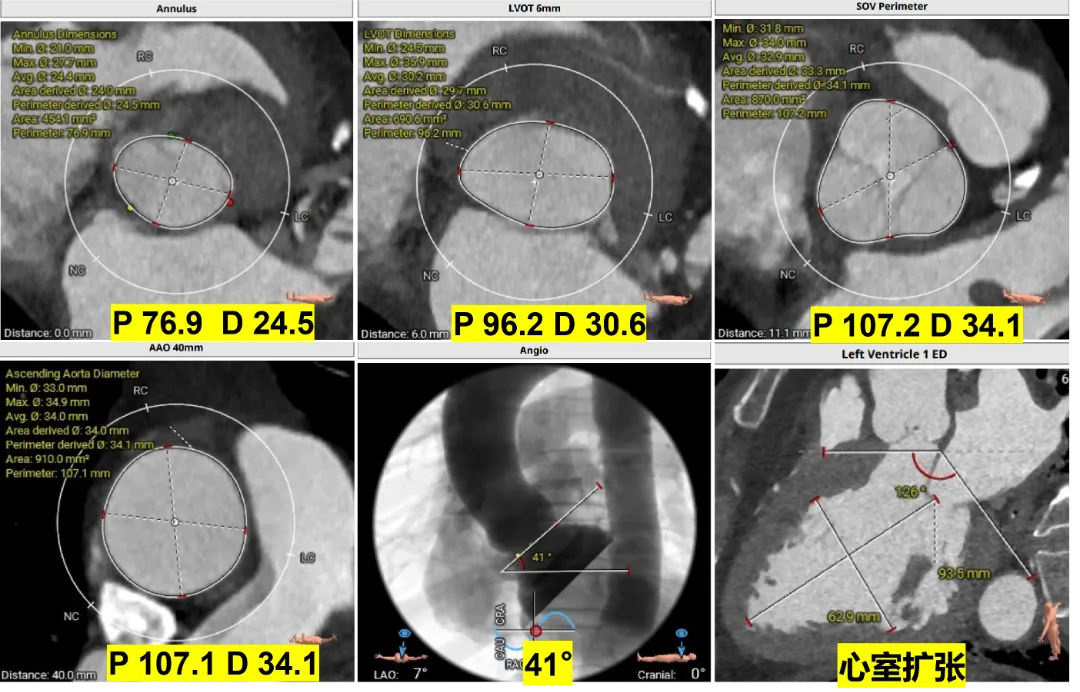

Case 1

大瓣环PAR伴有瓣叶脱垂、心室扩张心力衰竭

术前CT评估

根据瓣环与 LVOT-6 mm 平面,选择:M 号 TaurusTrio,瓣环可提供4.3%oversize